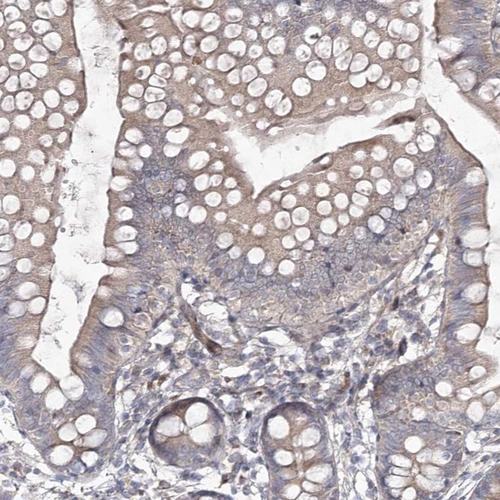

Immunohistochemical staining of human small intestine shows weak cytoplasmic positivity in glandular cells.